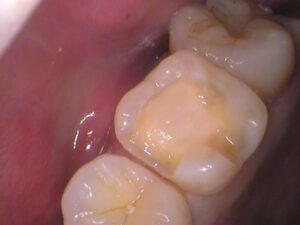

広範囲の虫歯でしたので、その分歯も削らなければなりません。

当院では最小限に虫歯を取り除くよう心掛けています。

歯の内部の神経までは達していませんでしたが、

神経近くまで虫歯がありました。

削った表面をレジンでコーティングして、

歯の形を整えていきます。

後は、歯型を取っていきましょう。